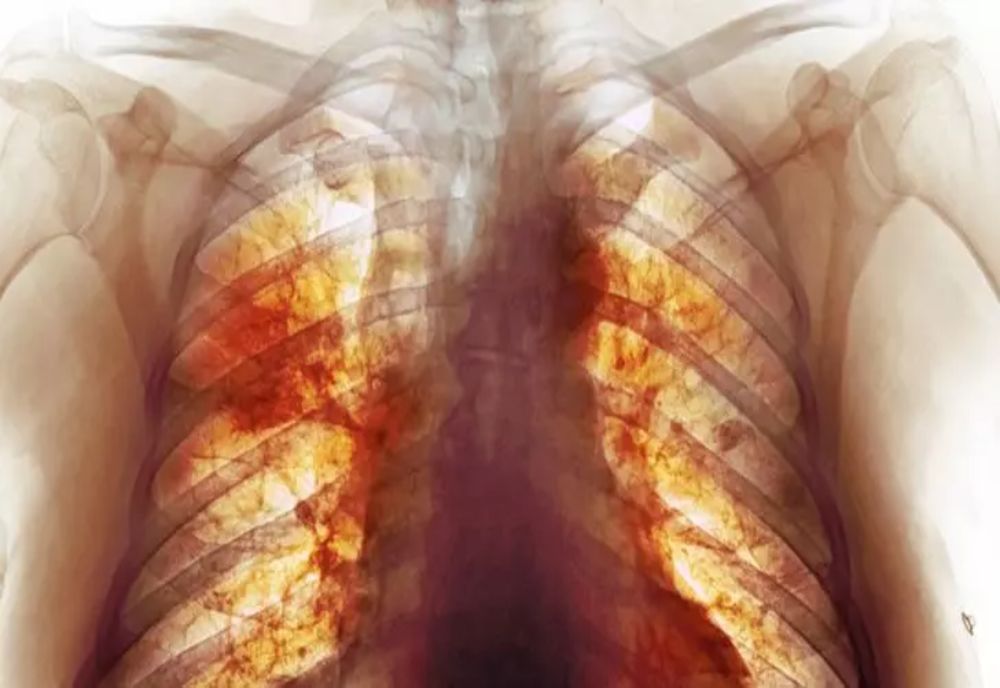

Pentru marea majoritate a pacienților infectați, Covid începe și se termină în plămâni. Într-o fotografie făcută publică de National Geographic, se poate vedea cât de grav este afectat plămânul în infecția cu coronavirus. Imediat ce virusul se instalează în corp, sistemul imunitar reacționează. În unele cazuri, însă, consecințele sunt fatale.

Național Geographic a publicat o radiografie făcută la cel mai mare și performant computer tomograf - HiP-CT scan.

În imagine se vede impactul virusului Covid asupra plămânului unui pacient în vârstă de 54 de ani - vasele de sânge active sunt roșii, cele blocate sunt galbene și spațiile aeriene sunt colorate cu cyan (albastru-verzui). IMAGINEA POATE FI VĂZUTĂ AICI.

"Pentru prima dată în istoria medicinei, putem vedea cum arată un plămân trecut prin infecția cu coronavirus", a declarat Claire Walsh, profesor doctor în cadrul UCL (University College London).

Cu ajutorul computerului tomograf HiP, cercetătorii au putut observa adevărata dimensiune a dezastrului provocat de infecția cu coronavirus. Computerul tomograf permitea vizualizarea celor mai mici vase de sânge și chiar a celulelor.

Tehnica face posibilă realizarea unor imagini fidele a modului în care virusul Covid afectează organele interne. În plus, se poate vedea felul în care vasele de sânge din plămânii afectați sunt redesenate de boală.